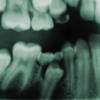

Every tooth consists of three different layers. From the outside, first there is Enamel (the outer layer of the teeth which is the hardest part of the body).

The second layer is Dentin (the inside hard layer) and then we have the Pulp (which is an empty space where the live tissue and nerve of each tooth is located)

If for any reason the pulp space is exposed to the outside, the tissue becomes contaminated and eventually infected. The exposure of pulp happens in many circumstances for example when you have a large cavity, or a fractured tooth. Your dentist can explain the exact reason for damage to this tissue. Regardless of the reason for this contamination or damage to pulp tissue, the treatment is usually Root canal treatment.

Root canal treatment is the process of going inside the pulp space and removing the infected and dead tissue. Then the space is disinfected and sealed with special materials.